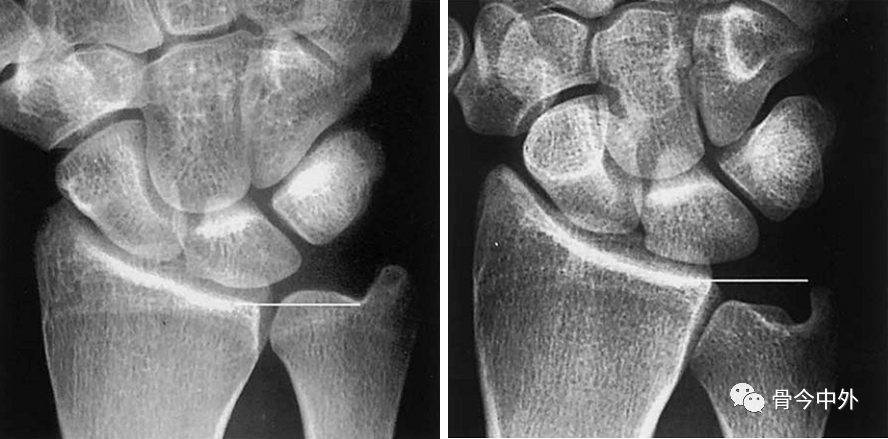

图5 左:正尺骨变异;右:负尺骨变异